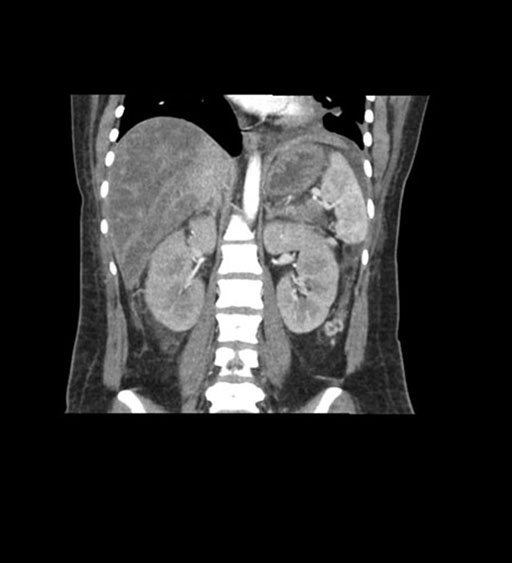

Imaging Analysis

Look through the patient's CT scan to identify any areas of concern for the necessary procedure.

Coronal Arterial

Based on initial findings, which issue(s) would you be most concerned about?